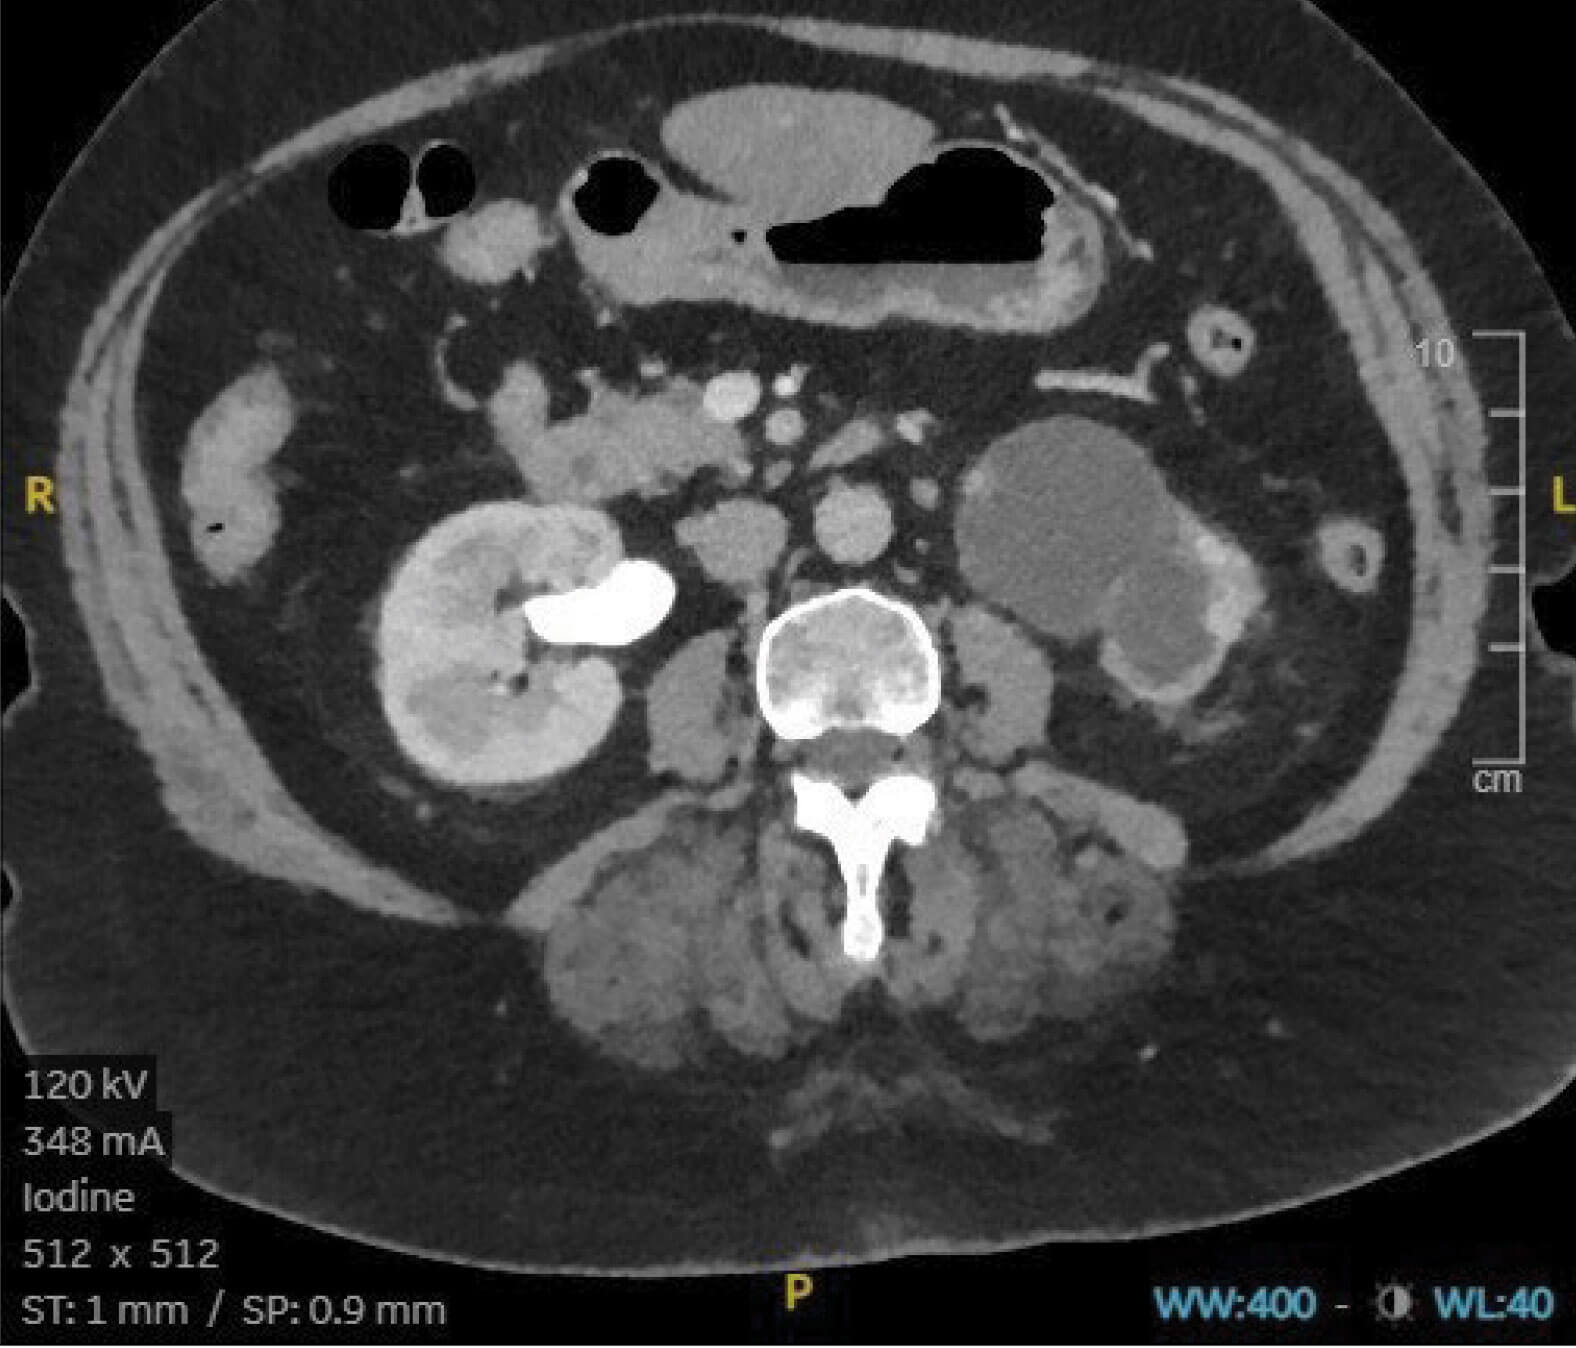

Figure 3.

- A 74-year-old female is noted on annual review to have a deterioration in her renal function. Following an ultrasound scan, a CT intravenous urogram (IVU) is performed, showing no hydroureter on either side, but what does Figure 3 show?

- A subsequent MAG-3 renogram confirms obstruction with 10% split function on the affected side. What are the congenital causes of this abnormality?

- A hydronephrotic left kidney with minimal renal cortex and no excretion of contrast into the collection system. Right kidney appears normal.

- Fifty percent of cases of congenital PUJ obstruction are the result of a crossing accessory renal vessel causing extrinsic obstruction of the proximal ureter. Other causes include ureteral hypoplasia with abnormal peristalsis preventing adequate drainage and high insertion of the ureter into the renal pelvis [8].

- PUJ obstruction is most commonly seen in the paediatric population, the left side being more commonly affected than the right [8].

- Hydronephrosis is commonly detected antenatally and up to 80% of these cases are as a result of PUJ obstruction. In paediatric patients it may also be found during investigation for other congenital abnormalities. Older children may present with loin pain associated with increased fluid intake, recurrent infection or pyelonephritis. In adults, chronic loin pain may also be associated with haematuria. Symptoms are often exacerbated by diuretics and high fluid intake [8].